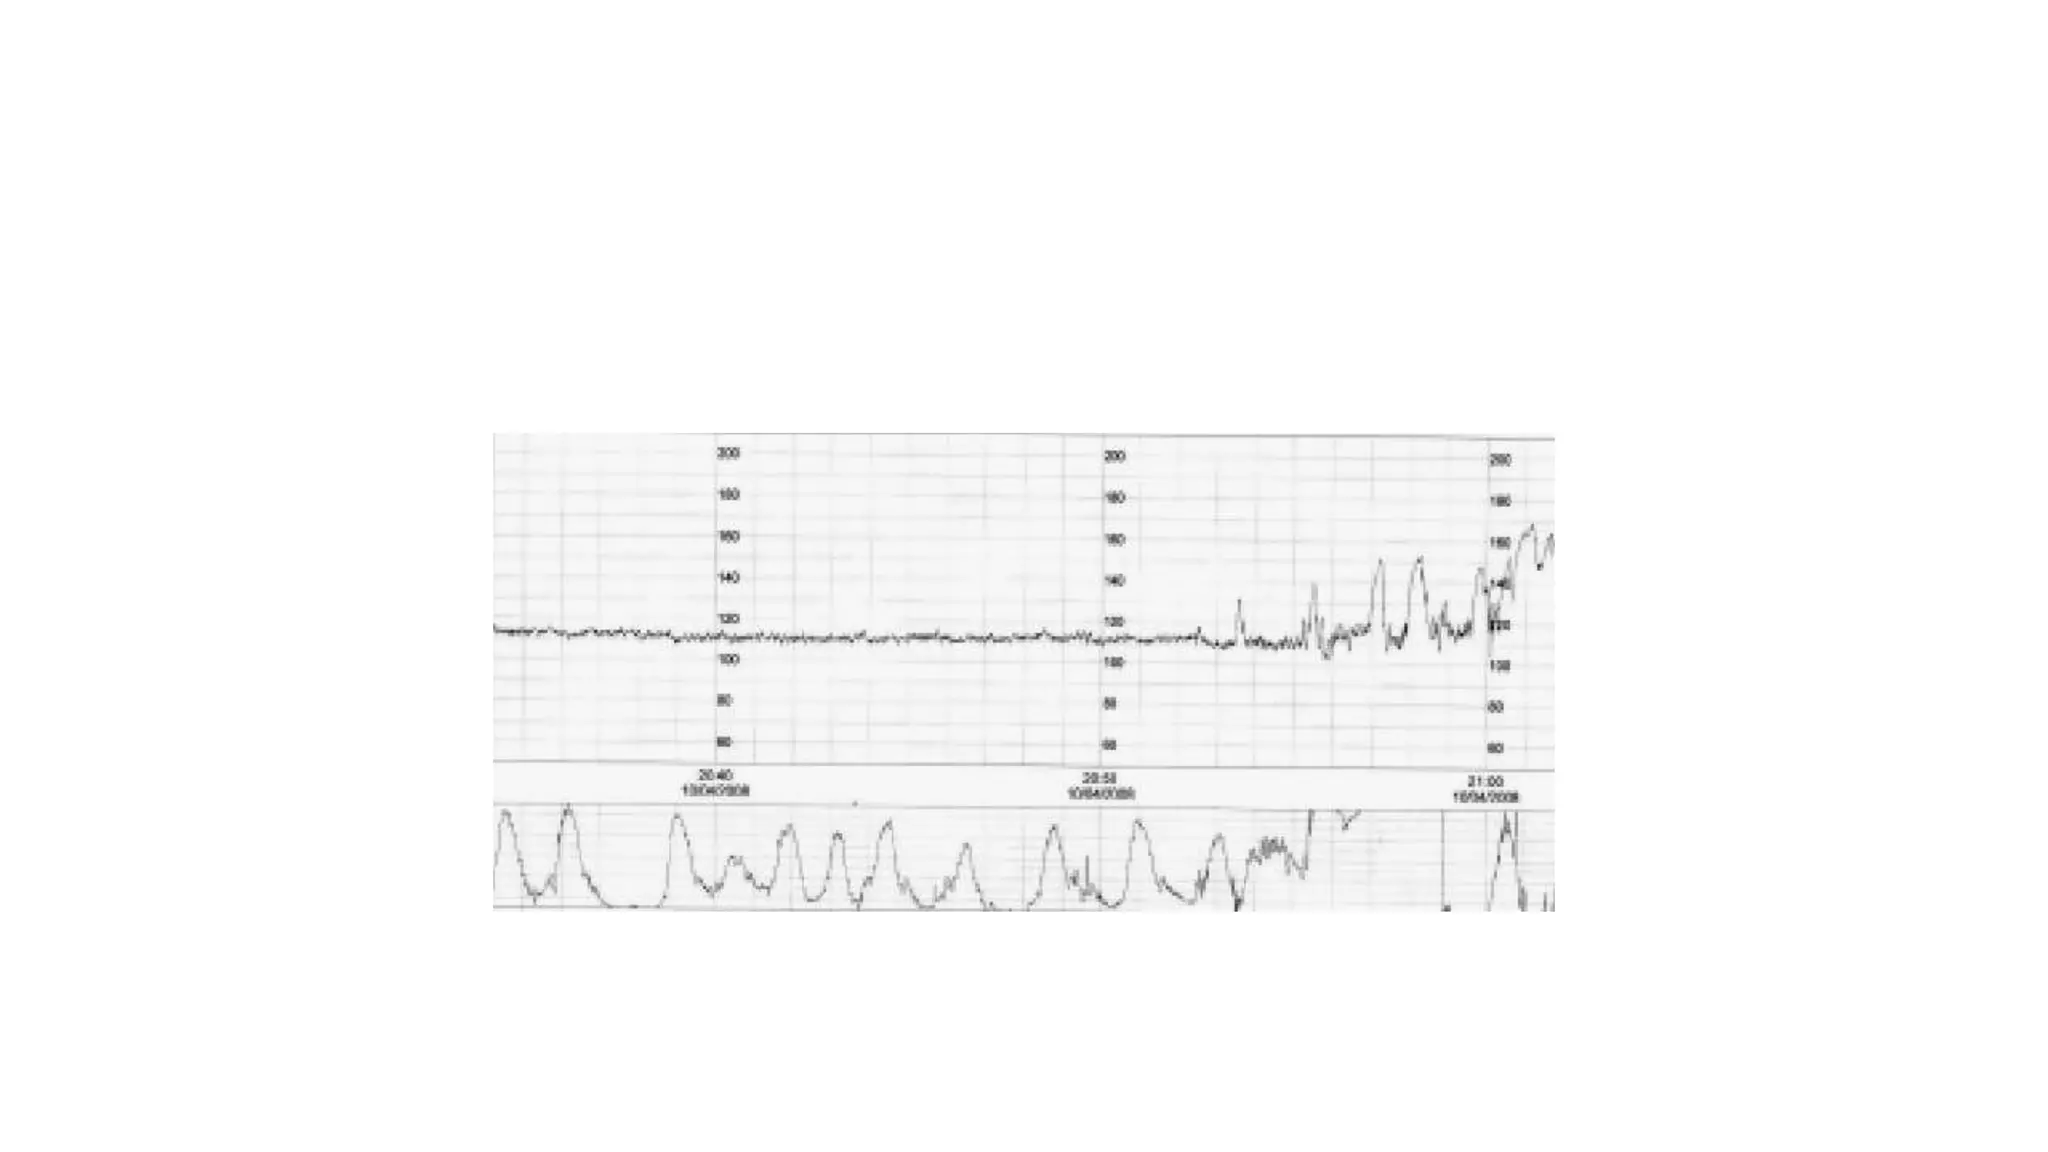

The document discusses key metrics for monitoring a baby's heart rate in utero, including the normal baseline rate of 100-160 bpm and variability. It also covers types of accelerations and decelerations that can occur, such as early or late, as well as bradycardia, which is an abnormally slow heart rate.